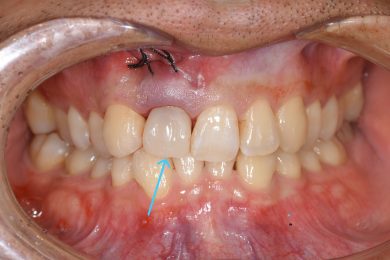

本日は、前歯のトラブルに対して

**抜歯即時インプラント+即日プロビジョナル(仮歯)**を行った症例をご紹介します。

初診時の対応

来院当日は、まず審美性と日常生活への影響を考慮し

👉 歯科用ボンドによる応急的な仮固定

を行いました。

治療の実際

今回行ったのは

👉 抜歯即時インプラント

👉 即時荷重

👉 即日プロビジョナル

です。

つまり

👉 抜歯したその日に

👉 インプラントを埋入し

👉 その日に仮歯を装着

という流れです。